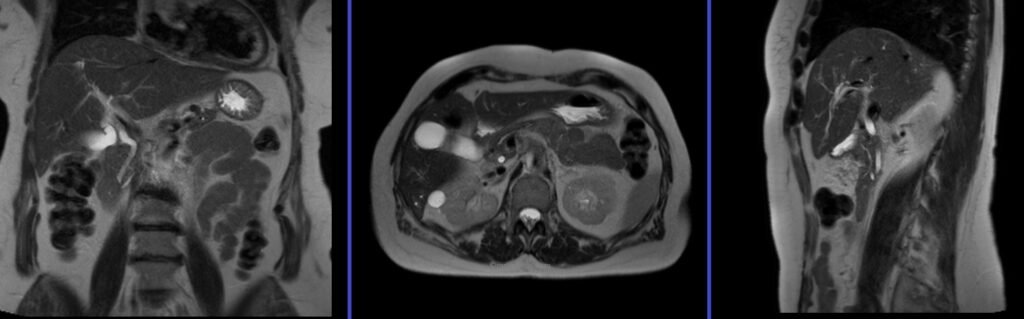

To localize and plan the sequences, it is essential to acquire a three-plane T2 HASTE localizer initially. These fast single-shot localizers have an acquisition time of under 25 seconds and are highly effective in accurately localizing abdominal structures.

T2 HASTE 5 mm breath hold coronal

Plan the coronal slices on the axial localizer and position the block horizontally across the liver as depicted. Verify the position in the other two planes. Establish an appropriate angle in the sagittal plane, aligning it vertically across the liver. Ensure that the slices adequately cover the entire liver, extending from the anterior abdominal wall to the erector spinae muscles. The phase direction should be from right to left to minimize ghosting artifacts from the lungs and heart. Employ phase oversampling to prevent wrap-around artifacts. Instruct the patient to hold their breath during image acquisition. (In our department, we typically advise patients to breathe in and out twice before providing the instruction to “breathe in and hold”.)

Parameters

TR 2000-2500 | TE 90-110 | FLIP 130 | NEX 1 | SLICE 5MM | MATRIX 320×256 | FOV 350 | PHASE R>L | OVERSAMPLE 50% | TRIGGER NO |